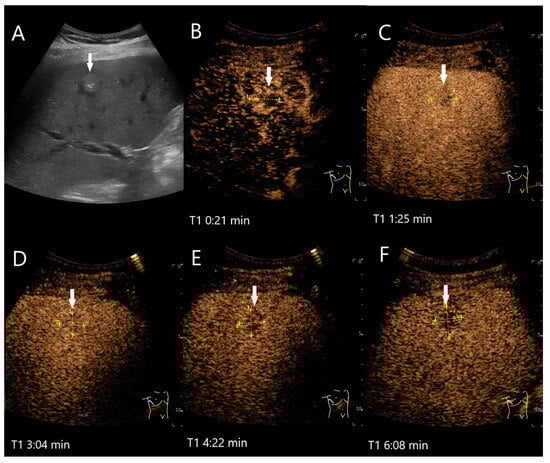

Figure 2.

Partially fibrosed hemangioma. As part of a staging examination for adenocarcinoma of the gastro-esophageal junction, a 19 mm, smoothly bordered hyperechoic lesion (arrow) with an implied hypoechoic rim and punctate echogenic reflexes is diagnosed in the liver (A). On CEUS, the small lesion (between the markings) shows a marginal contrast image that is not completely smooth (B). In the PVP after 1:25 min, most of the lesion is enhanced, but slightly less than the surrounding parenchyma and with a small portion that is clearly hypoenhanced (C). After 3:04 min, the lesion is slightly hypoenhanced (D), while after 4:22 min (E) and 6:08 min (F), the lesion shows an unequivocal hypoenhancement. The lesion did not clearly correspond to a hemangioma on computed tomography either. This was the reason for a US-guided biopsy. Histology revealed a hemangioma, partially fibrosed and with tiny calcifications.